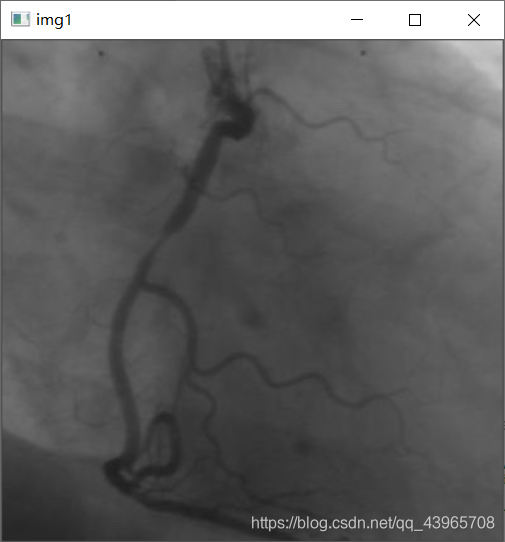

實現過程# -*- coding: utf-8 -*-’’’作者 : 丁毅開發時間 : 2021/5/9 16:30’’’import cv2import numpy as np# 圖像細化def VThin(image, array): rows, cols = image.shape NEXT = 1 for i in range(rows):for j in range(cols): if NEXT == 0:NEXT = 1 else:M = int(image[i, j - 1]) + int(image[i, j]) + int(image[i, j + 1]) if 0 < j < cols - 1 else 1if image[i, j] == 0 and M != 0: a = [0]*9 for k in range(3):for l in range(3): if -1 < (i - 1 + k) < rows and -1 < (j - 1 + l) < cols and image[i - 1 + k, j - 1 + l] == 255:a[k * 3 + l] = 1 sum = a[0] * 1 + a[1] * 2 + a[2] * 4 + a[3] * 8 + a[5] * 16 + a[6] * 32 + a[7] * 64 + a[8] * 128 image[i, j] = array[sum]*255 if array[sum] == 1:NEXT = 0 return imagedef HThin(image, array): rows, cols = image.shape NEXT = 1 for j in range(cols):for i in range(rows): if NEXT == 0:NEXT = 1 else:M = int(image[i-1, j]) + int(image[i, j]) + int(image[i+1, j]) if 0 < i < rows-1 else 1if image[i, j] == 0 and M != 0: a = [0]*9 for k in range(3):for l in range(3): if -1 < (i-1+k) < rows and -1 < (j-1+l) < cols and image[i-1+k, j-1+l] == 255:a[k*3+l] = 1 sum = a[0]*1+a[1]*2+a[2]*4+a[3]*8+a[5]*16+a[6]*32+a[7]*64+a[8]*128 image[i, j] = array[sum]*255 if array[sum] == 1:NEXT = 0 return imagearray = [0, 0, 1, 1, 0, 0, 1, 1, 1, 1, 0, 1, 1, 1, 0, 1, 1, 1, 0, 0, 1, 1, 1, 1, 0, 0, 0, 0, 0, 0, 0, 1, 0, 0, 1, 1, 0, 0, 1, 1, 1, 1, 0, 1, 1, 1, 0, 1, 1, 1, 0, 0, 1, 1, 1, 1, 0, 0, 0, 0, 0, 0, 0, 1, 1, 1, 0, 0, 1, 1, 0, 0, 0, 0, 0, 0, 0, 0, 0, 0, 0, 0, 0, 0, 0, 0, 0, 0, 0, 0, 0, 0, 0, 0, 0, 0, 1, 1, 0, 0, 1, 1, 0, 0, 1, 1, 0, 1, 1, 1, 0, 1, 0, 0, 0, 0, 0, 0, 0, 0, 0, 0, 0, 0, 0, 0, 0, 0, 0, 0, 1, 1, 0, 0, 1, 1, 1, 1, 0, 1, 1, 1, 0, 1, 1, 1, 0, 0, 1, 1, 1, 1, 0, 0, 0, 0, 0, 0, 0, 1, 0, 0, 1, 1, 0, 0, 1, 1, 1, 1, 0, 1, 1, 1, 0, 1, 1, 1, 0, 0, 1, 1, 1, 1, 0, 0, 0, 0, 0, 0, 0, 0, 1, 1, 0, 0, 1, 1, 0, 0, 0, 0, 0, 0, 0, 0, 0, 0, 1, 1, 0, 0, 1, 1, 1, 1, 0, 0, 0, 0, 0, 0, 0, 0, 1, 1, 0, 0, 1, 1, 0, 0, 1, 1, 0, 1, 1, 1, 0, 0, 1, 1, 0, 0, 1, 1, 1, 0, 1, 1, 0, 0, 1, 0, 0, 0]# 顯示灰度圖img = cv2.imread(r'C:UserspcDesktopvas0.png',0)cv2.imshow('img1',img)# 自適應閾值分割img2 = cv2.adaptiveThreshold(img, 255, cv2.ADAPTIVE_THRESH_MEAN_C, cv2.THRESH_BINARY, 17, 4)cv2.imshow(’img2’, img2)# 圖像反色img3 = cv2.bitwise_not(img2)cv2.imshow('img3', img3)# 圖像擴展img4 = cv2.copyMakeBorder(img3, 1, 1, 1, 1, cv2.BORDER_REFLECT)cv2.imshow('img4', img4)contours, hierarchy = cv2.findContours(img4, cv2.RETR_EXTERNAL, cv2.CHAIN_APPROX_NONE)# 消除小面積img5 = img4for i in range(len(contours)): area = cv2.contourArea(contours[i]) if (area < 80) | (area > 10000):cv2.drawContours(img5, [contours[i]], 0, 0, -1)cv2.imshow('img5', img5)num_labels, labels, stats, centroids = cv2.connectedComponentsWithStats(img5, connectivity=8, ltype=None)# print(stats)s = sum(stats)img6 = np.ones(img5.shape, np.uint8) * 0for (i, label) in enumerate(np.unique(labels)): # 如果是背景,忽略 if label == 0:# print('[INFO] label: 0 (background)')continue numPixels = stats[i][-1] div = (stats[i][4]) / s[4] # print(div) # 判斷區域是否滿足面積要求 if round(div, 3) > 0.002:color = 255img6[labels == label] = colorcv2.imshow('img6', img6)# 圖像反色img7 = cv2.bitwise_not(img6)# 圖像細化for i in range(10): VThin(img7, array) HThin(img7, array)cv2.imshow('img7',img7)# 邊緣檢測img8 = cv2.Canny(img6, 80, 255)cv2.imshow('img8', img8)# 使灰度圖黑白顛倒img9 = cv2.bitwise_not(img8)cv2.imshow('img9', img9)cv2.waitKey(0)

運行結果